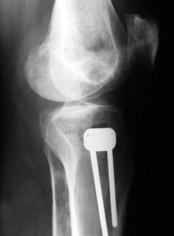

Yesterday one leg was done (my plan to make both in one session were cancelled because of external reasons). So much exciting and useful experience.

The osteotomy line i planned to make a bit oblique, but not so as you suggested. But at the moment of osteoclasis after corticotomy through the anterior stab wound the line became almost as you described. Now problem is how to reproduce thee line at the next leg ;-)

The prominent fragment seems to be useful for cosmetic purposes, because aesthetic guys perform medialization of the distal fragment to gain attractive curve at the medial side of the leg. Also all locking options became available - initially i planned to engage only two most

proximal 45 degree holes.

I cut the fibula because i externally rotated the distal fragment by 6-7 degrees. With only angular correction it didn't show any displacement.

Today CT for estimation of rotation was performed, results i will see only tomorrow. Rotation of the operated limb can be corrected with the second surgery. Comments/critics are welcome.

Снимки в приложении - фас сравнительный с неоперированной ногой. Жду критики.

Впрос про остеотомию большеберцовой непраздный. Эта получилась при надломе несколько более наклонно, чем я делал (сейчас проблема,

как на второй ноге сделать так же). Вот этот высоящий "зуб" центрального отломка не заменит ли в плане косметики то, что получается при медиализации дистального?

Nice job!

It is very interesting to me that as you have derotated the tibia you have centred the patella, I think and the prox tibia looks much more anatomic.

The analysis in the attached images is direct, just using the tools.

Tibial tilt is perhaps more than you want but the tibial correction is to 90 (very slight over

correction.

Will need full length views to tell us about the hka but it appears neutral.

Measurements took 4 mins